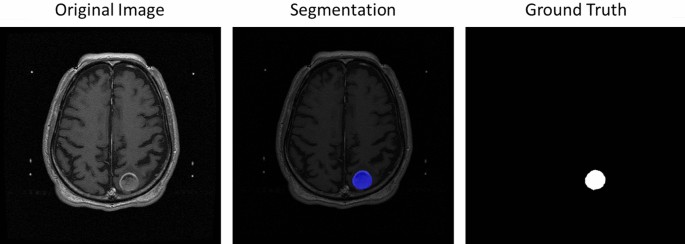

Figure 6 visualize the segmentation results. The left-hand side was the original MRI image and the right-hand side shown the ground truth where the tumors was in the slice. The middle is the segmentation, the blue part was the true positive, the green region was the false negative and the area in red was false positive. More segmentation result shown in Figure 7.

Selected the tumor segmentation results compared in slice-by-slice.